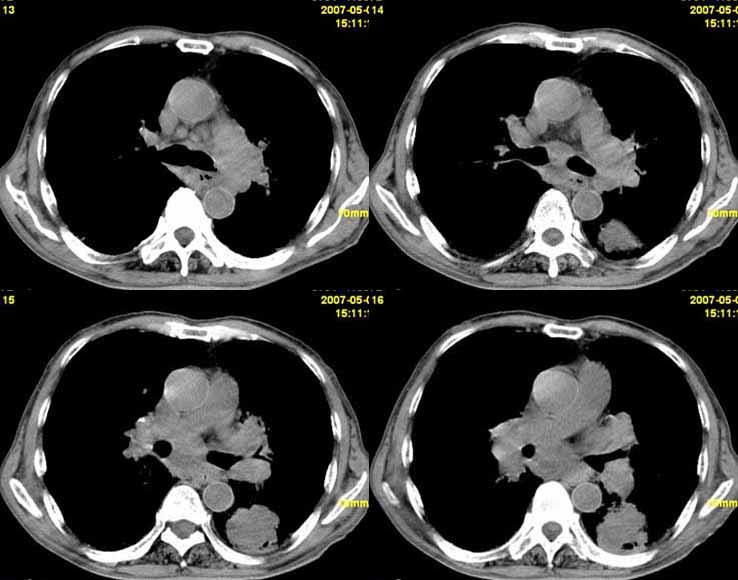

以下是引用小初学者在2007-5-12 11:09:00的发言:[br][br]双肺弥漫性质纤维化(考虑矽肺所致),并发左肺下叶背段周围性肺癌纵隔淋巴转移。

以下是引用zhangzhongshou在2007-5-12 12:09:00的发言:[br]1、左下叶背段周围型肺癌左肺门及纵隔淋巴结转移可能性大。[br]2、弥漫性肺气肿(双侧)。[br]3、双肺间质纤维化。

以下是引用老爱克斯新网客在2007-5-12 12:54:00的发言:[br]1周围型肺癌纵隔肺门淋巴结转移,2肺间质纤维化,